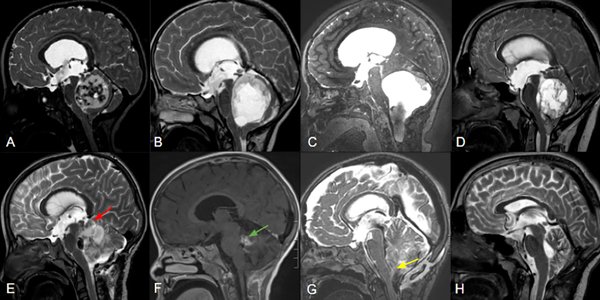

Figura 2. Cortes sagitales de RM de pacientes con APcs asociados a invasión troncoencefálica a distintos niveles: mesencefálica (A), pontina (B) y bulbar (C), con sus controles postoperatorios respectivos (E:G) señalando remanentes tumorales (flechas roja, verde y amarilla). La figura D demuestra una lesión predominantemente sólida y central que comprime pero no invade el tronco, la cual pudo ser completamente resecada (H).

El grado de resección se categorizó como resección total (RT), resección casi total (RCT), resección subtotal (RST) basada en la observación intraoperatoria del neurocirujano y RM con gadolinio postoperatoria analizada por especialistas en neuroimágenes (Figura 2). La RT correspondió a los casos en los que todos los hallazgos de imagen postoperatorios fueron negativos de acuerdo con la apreciación de los neurocirujanos. La RCT correspondió mayoritariamente a los casos en los que quedó un residuo tumoral mínimo < 2%, como en los casos de invasión del IV ventrículo, o cuando se consideró resección completa, pero aún se identificaron restos mínimos en la RM postoperatoria. RST, consecuentemente corresponde a cualquier resección que no alcanzaba los criterios anteriores.

Se incluyeron un total de 100 pacientes con un seguimiento medio de 53,9 meses (rango 12-156). El 54% de la población analizada era de sexo femenino y la edad media fue de 7,6 años. La localización más frecuente fue la central (64%), y 29% de los casos correspondió a lesiones sólidas. El 24% de los tumores se asoció con invasión del tronco encefálico o de los pedúnculos cerebelosos (Figura 2).